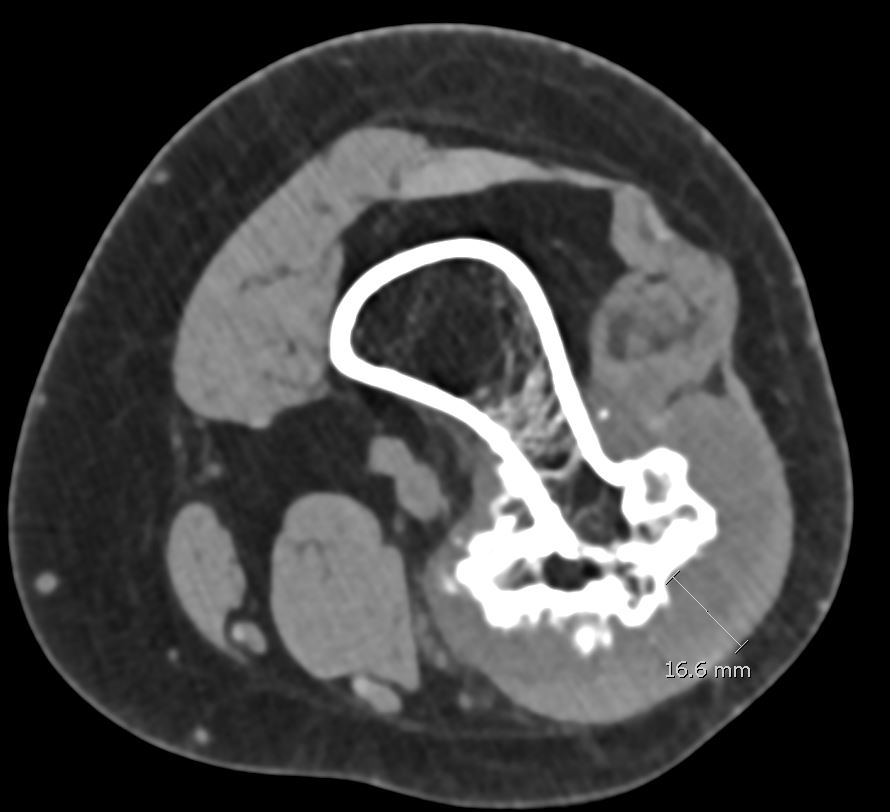

Suspicious features

- growth after maturity

- increased thickness of cartilage cap on CT / MRI - > 2 cm

- increasing pain

- increased calcification / bony erosion / lytic areas on xray

- septal enhancement after MRI with gadolinium

- MRI / CT of 64 benign osteochondromas and 34 secondary chondrosarcomas

- cartilage cap 2 cm or more 100% sensitive and 98% specific for secondary chondrosarcoma

CT

Cortex and medullary cavity of normal bone contiguous with osteochondroma

MRI

Cartilage cap iso-intense with hyaline cartilage